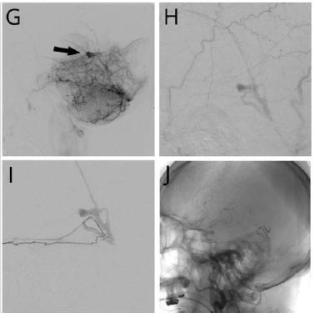

考虑到之前的影像检查未能检测出潜在的静脉血栓,我们对患者还是进行了脑血管造影检查。静脉期示直窦硬脑膜动静脉瘘(dural arteriovenous fistula, dAVF)(Borden分级 III级),直窦中段短节段闭塞。可见多重血管供应包括左侧脑膜中动脉后支、左侧大脑后动脉脑膜支以及Davidoff和Schechter动脉。经动脉栓塞后dAVF血流减少70%。经静脉未能执行是由于导管无法穿过直窦血栓,提示血栓形成是慢性形成的。

症状性dAVF的主要治疗方法是血管内栓塞。栓塞的目的是治疗静脉高压和消除直接皮质静脉引流。急性期不明原因的CVST通常抗凝治疗6-12个月。该患者CVST慢性形成的机制仍不明确,由于患者静脉高压进行性加重导致梗死和脑实质出血,抗凝治疗带来的获益是大于其风险的。